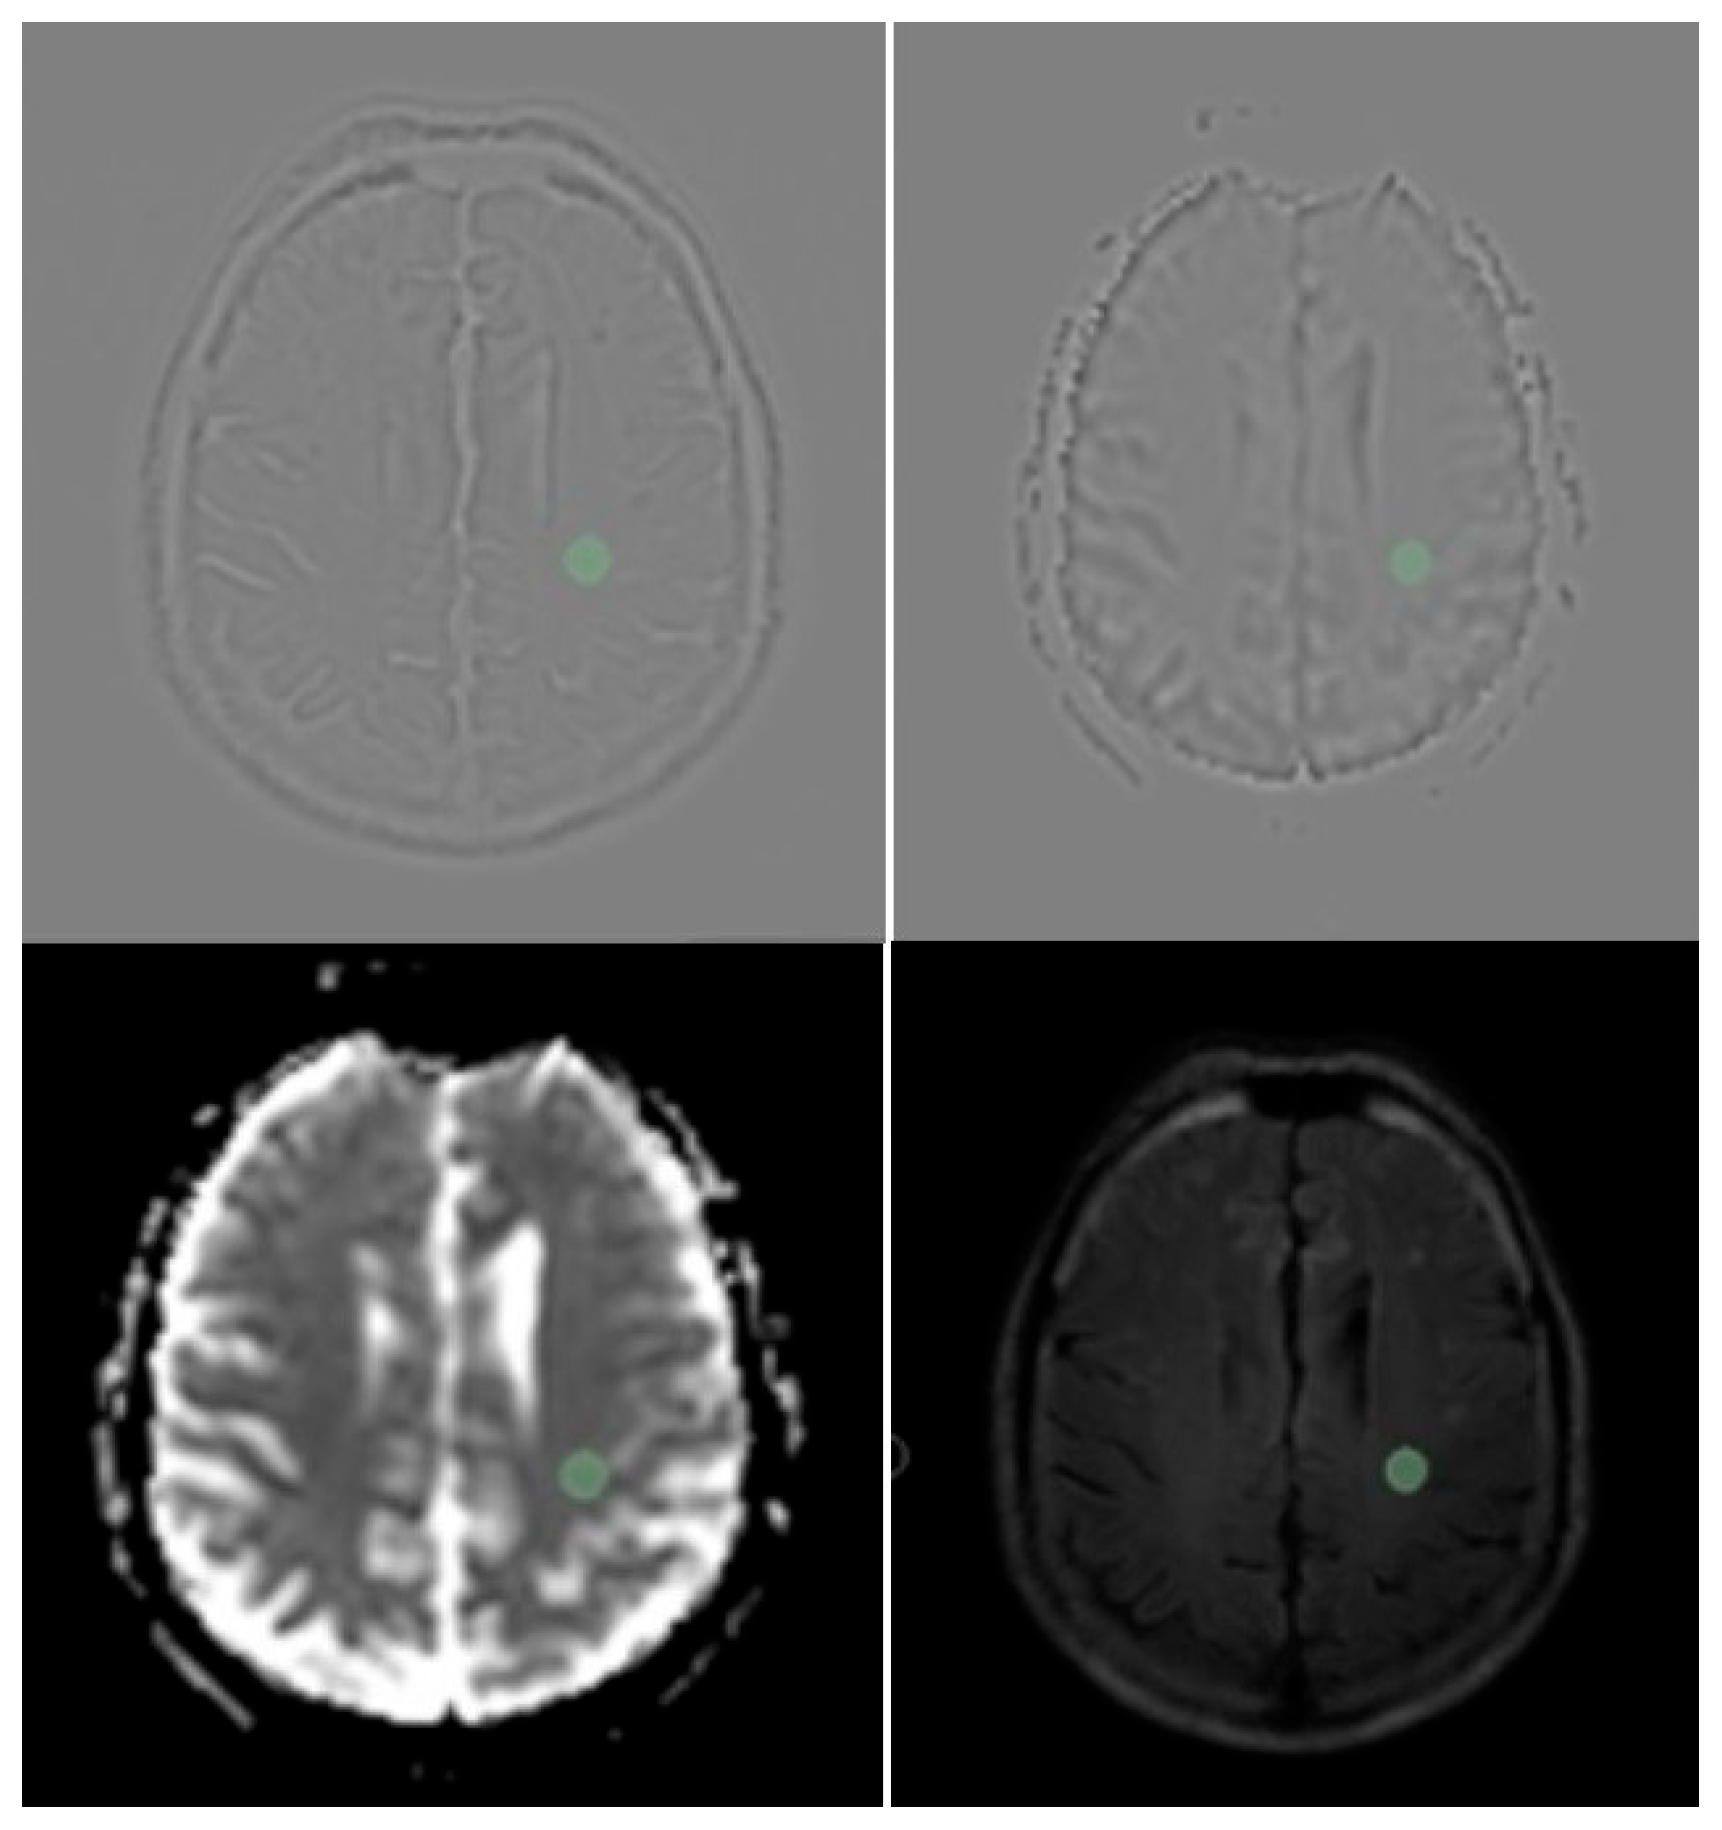

In this study, centrum semiovale radiomics features in patients with different global PVS scores are compared. Normal-appearing centrum semiovale was defined as areas without any signal alterations on T1, T2 and DW images and involving no signal alterations in a 1 cm distance around the specified region of interest (ROI). A circular area with a diameter of 1 cm and meeting the conditions to define “normal appearing centrum semiovale area” was selected for further assessment [11] (Figure 2).

Data of the patients was exported into 3DSlicer version 4.9.0 [13] software in DICOM file format. This allowed 116 features to be extracted using the published “Radiomics” extension. Detailed descriptions of these features were published by Zwanenburg et al. [14].

Figure 2. Centrum semiovale sampling of white matter with 3Dslicer software in LoG filtered and unfiltered FLAlR and ADC images. (Note that in FLAlR images sampling Rol (green circle) is at least 1 cm far from T2 hyperintense lesions).